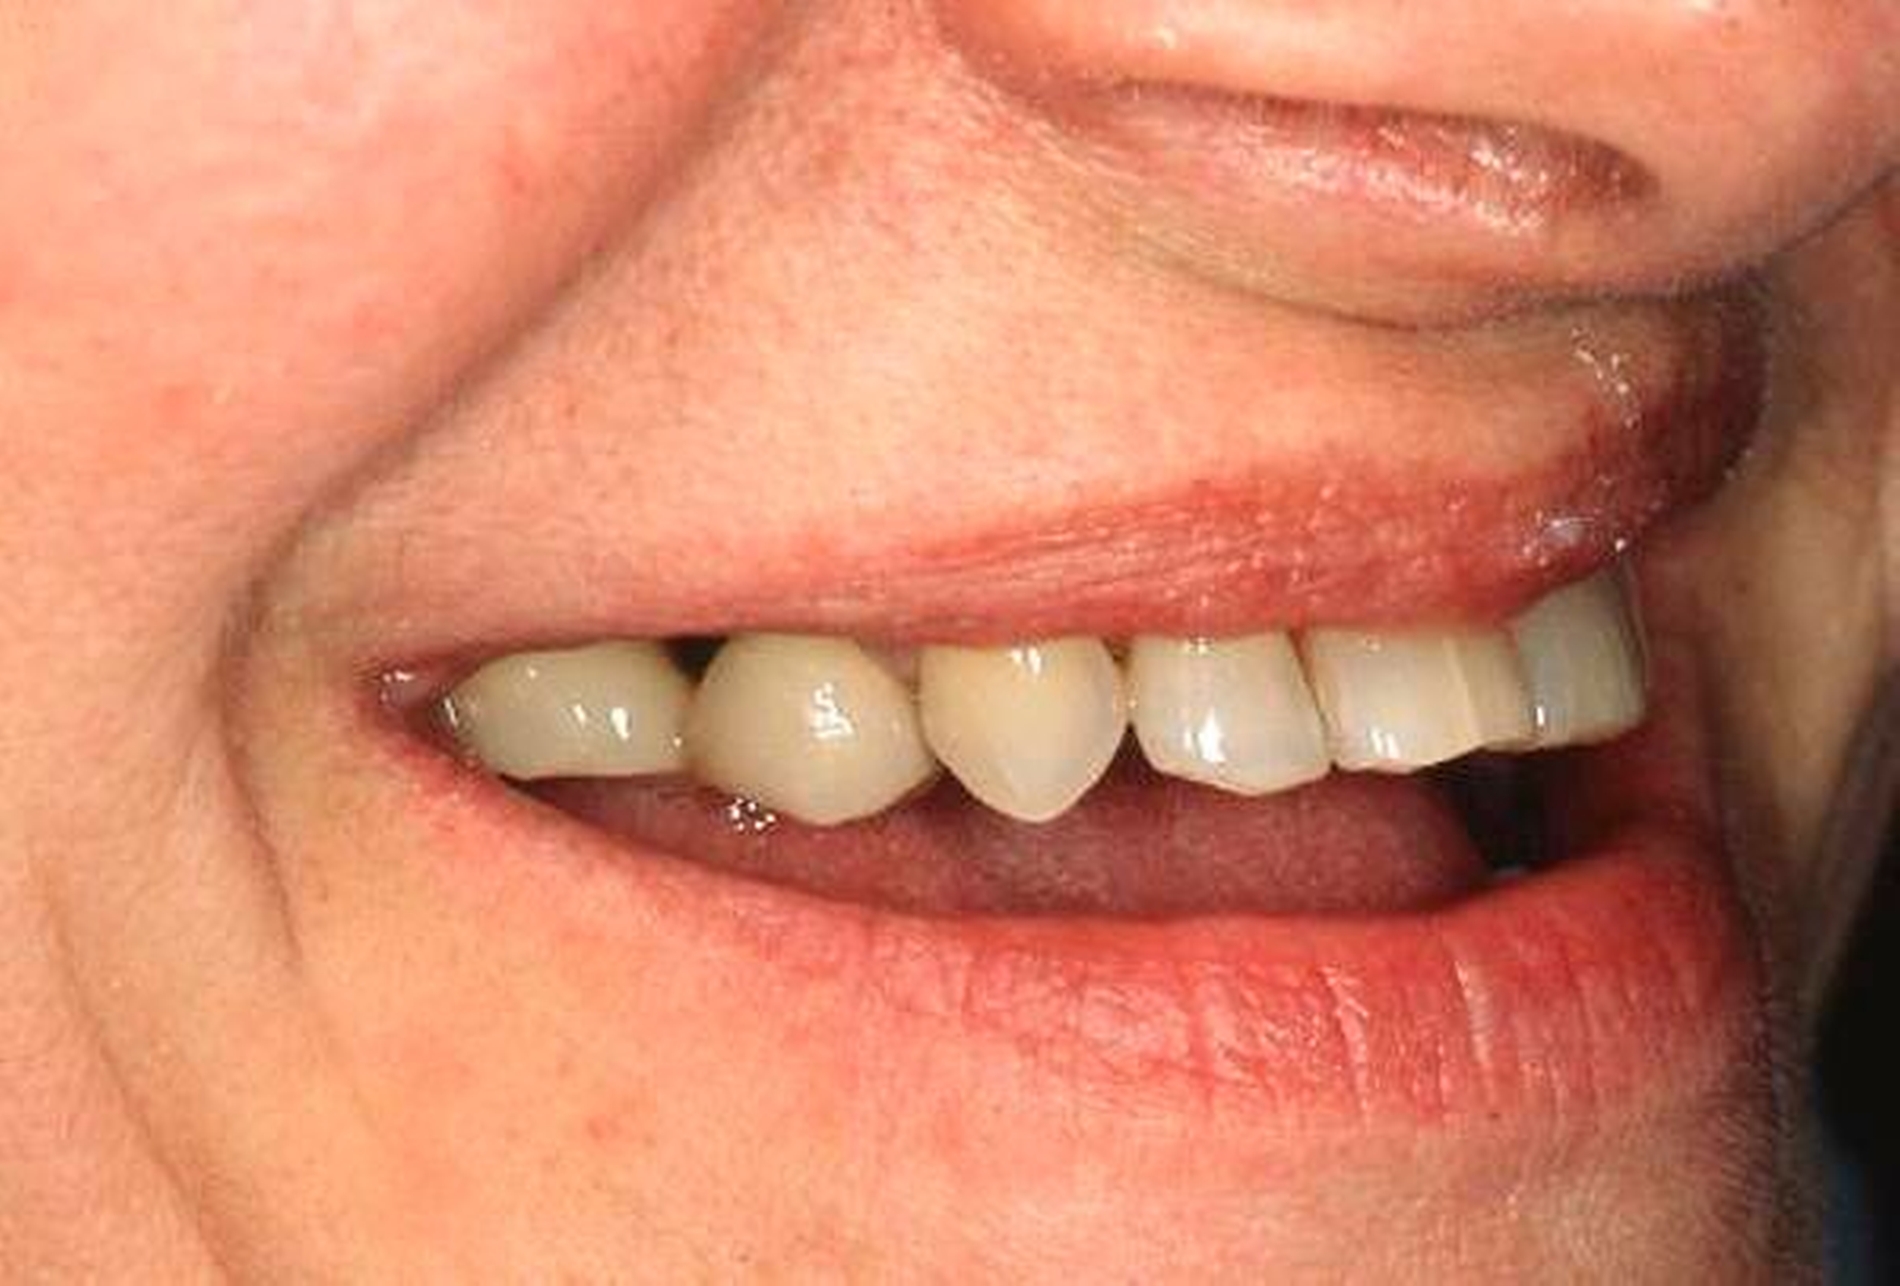

Abbildung 1a bis 1f: Direkte Überkronung im Frontzahnbereich (R1-Technik)

In den Abbildungen 1 bis 3 werden Optionen für frugale Interventionen auf restaurativem Sektor aufgeführt. Es handelt sich um direkte Vollüberkronungen im Frontzahnbereich (hier: hergestellt in R1-Technik / einphasig) (Abbildung 1), direkte Teilüberkronungen im Seitenzahnbereich (hier: hergestellt in R1-Technik / einphasig) (Abbildung 2), Reparatur-Restaurationen im Seitenzahnbereich (hier: hergestellt in R2-Technik / zweiphasig) (Abbildung 3). Technische Einzelheiten zur Vorgehensweise und den Ergebnissen sind an anderer Stelle beschrieben (Literatur siehe oben).

Am Beispiel von Abbildung 1 (stark zerstörte Zahnkrone eines Schneidezahns) kann das Prinzip der frugalen Intervention erläutert werden:

Früher wurde für die hier beschriebene Ausgangssituation folgendes Procedere gewählt:

Wurzelkanalbehandlung des vitalen Zahns als Voraussetzung für eine Stiftversorgung

Einsetzen eines Wurzelkanalstifts

Einsetzen einer indirekt gefertigten Stiftkrone

Durch die Erfolge der Adhäsiv- und Komposittechnik kann heute folgendermaßen vorgegangen werden:

Verzicht auf Wurzelkanalbehandlung / Erhaltung der Vitalität des Zahns

Verzicht auf Wurzelkanalstift

direkte minimalinvasive Kompositkrone (Verzicht auf indirekte Vorgehensweise)

Die potenziellen medizinischen und ökonomischen Vorteile dieser frugalen Intervention sind vielfältig:

Schonend: Die oralen Strukturen werden geschont und die Versorgung ist hinreichend stabil. Durch den Verzicht auf Wurzelkanalstifte wird das Wurzelfrakturrisiko reduziert. Zudem können Material-, Geräte- und Personalressourcen aus Praxis und Techniklabor, die beim klassischen Vorgehen anfielen, reduziert werden.

Bezahlbar: Hier ist anzumerken, dass die Kosten unter anderem von der zahnärztlichen Expertise abhängig sind: Zahnärzte, die mit direkten Restaurationen große Erfahrung haben, können zügiger und mit besserem Erfolg arbeiten als Kollegen mit geringerer Erfahrung auf diesem Gebiet; die Behandlung ist gleichwohl anspruchsvoll und deshalb nicht „billig“. Eine direkte Vorgehensweise kann, muss aber nicht automatisch zeit- und kostensparender sein als eine Versorgung mit indirekt hergestellten Werkstücken.

Gut genug: Ästhetische Feinheiten lassen sich bei direkten Restaurationen nicht immer in gleicher Perfektion einarbeiten wie bei indirekt gefertigten Kronen, auch die Stabilität des Hochglanzes lässt bei einigen Kompositpräparaten noch zu wünschen übrig. Andererseits erlauben die direkten Verfahren inzwischen mitunter sehr flexible Vorgehensweisen, die sich auch mit Farb- und Formkorrekturen von Zähnen kombinieren lassen. Die Erwartungen eines großen Teils der Patienten werden hinreichend erfüllt und die Nutzen-Risiko-Relationen wie auch die Aufwand-Kosten-Relationen erscheinen – wenn auch nicht durchgängig – so doch zumindest in vielen Fällen günstig.